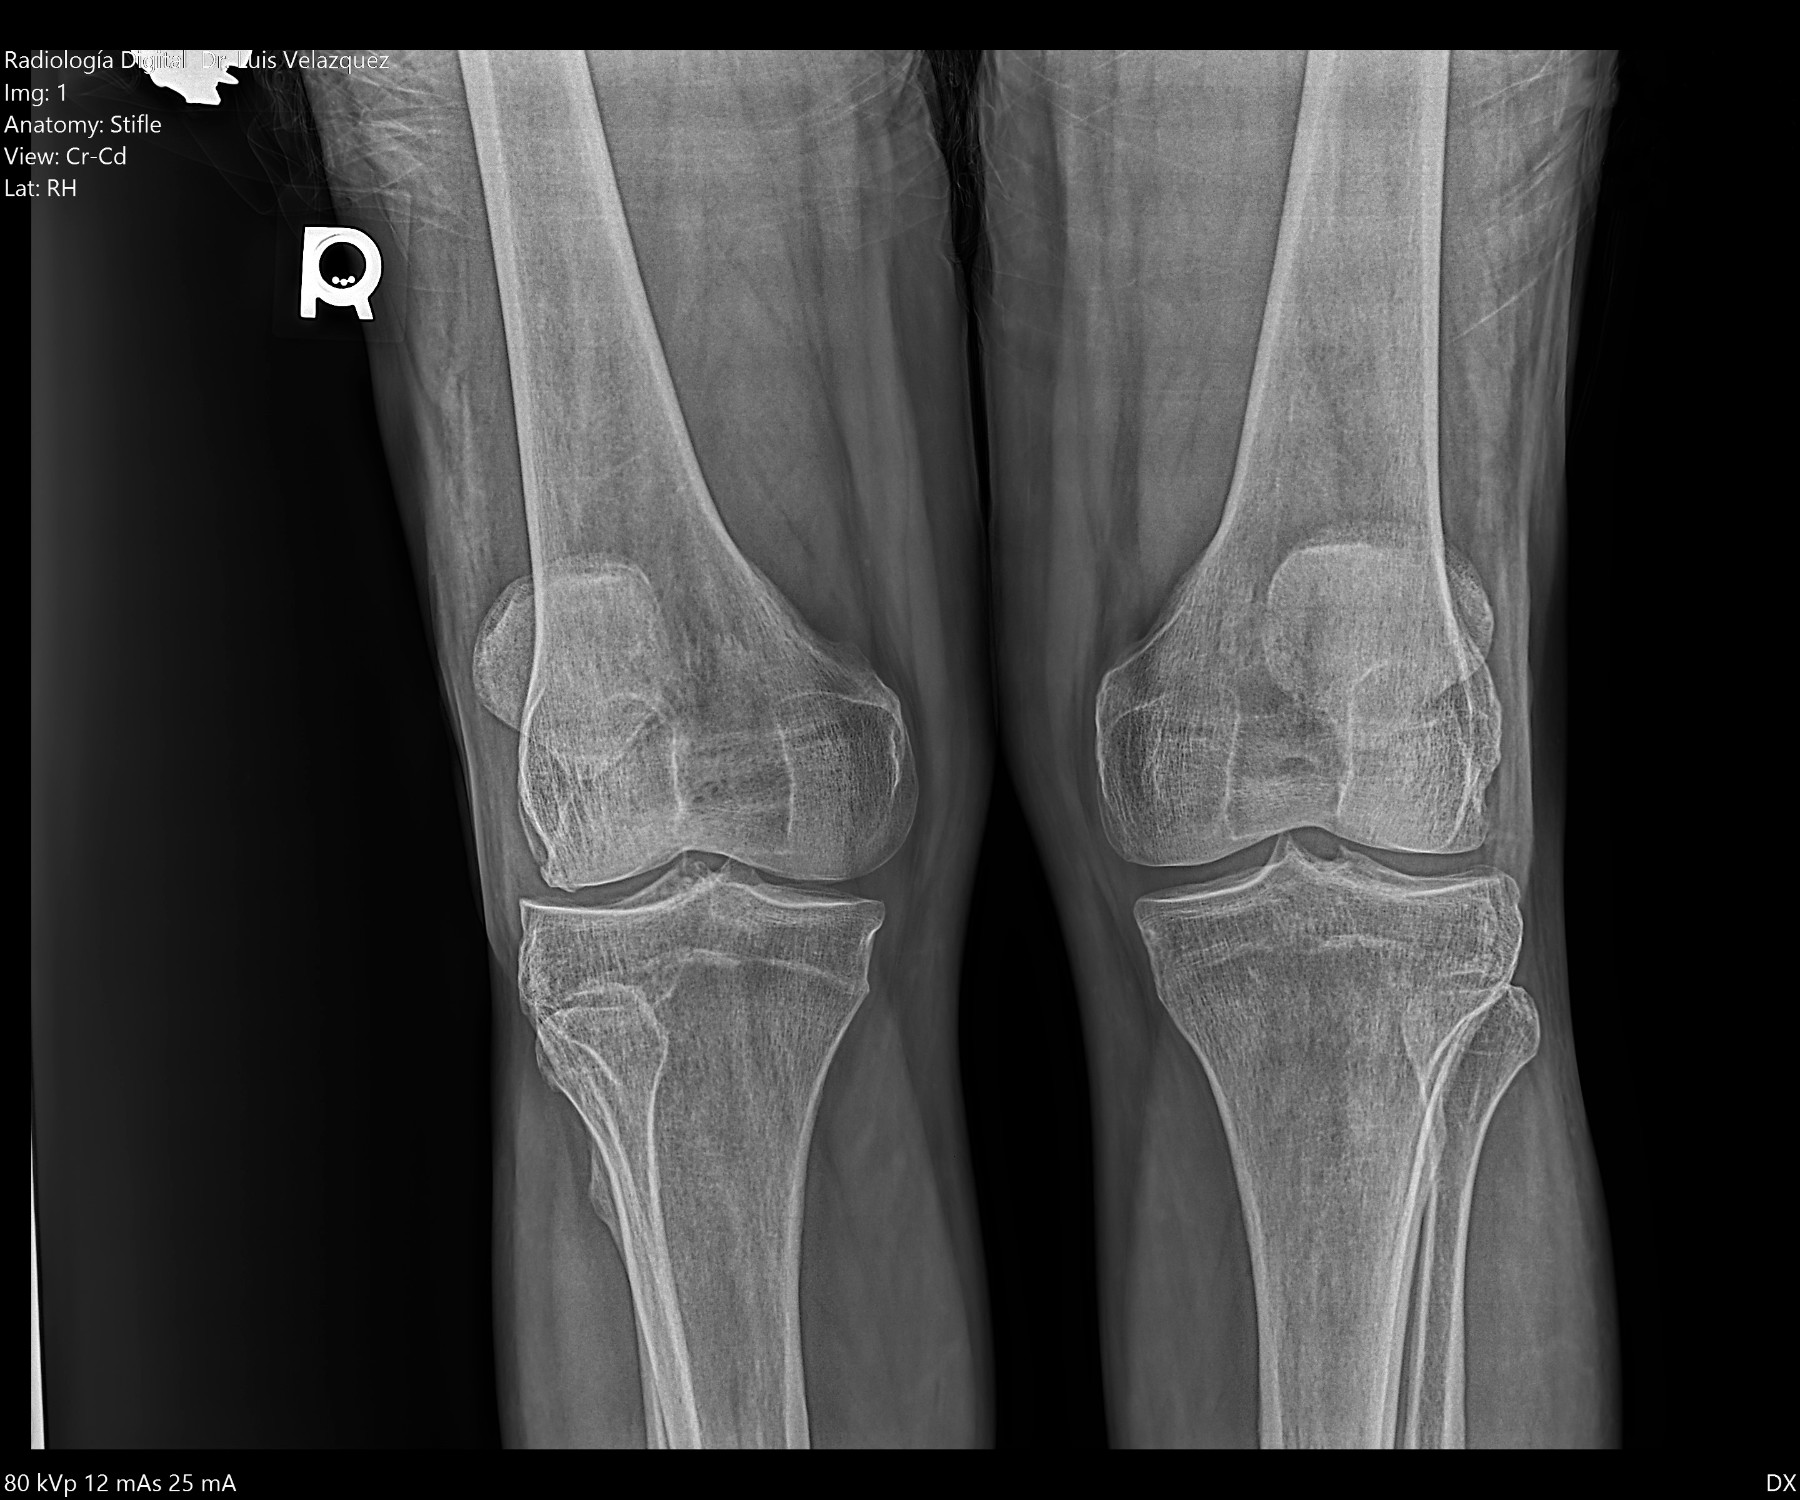

Radiología Digital como Herramienta Complementaria en el Dictamen de Bienes Muebles

Desde el descubrimiento de los rayos “X” y las placas radiográficas por Wilhelm Conrad Roentgen y su posterior difusión a través de la Asociación Físico médica de Wurzburg el 28 de diciembre de 1895, que fue la primera asociación que habló de los nuevos rayos que podían penetrar el cuerpo y fotografiar los huesos, ha habido muchos cambios tanto en la forma de obtener, procesar e incluso en la forma de visualizar, manejar y almacenar las placas radiográficas.